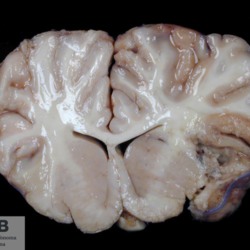

Pàgina anterior de 637 Pàgina següent 3181 total Canine Specie: Canine Organ: Brain Lesion: Glioma Lesion modifier: - Disease: - Files/Expedient: N-338/09 Not viewed Canine Specie: Canine Organ: Brain Lesion: Glioma Lesion modifier: - Disease: - Files/Expedient: N-338/09 Not viewed Feline Specie: Feline Organ: Spinal cord Lesion: Lymphoma Lesion modifier: - Disease: - Files/Expedient: N-331/09 Not viewed Equine Specie: Equine Organ: Brain Lesion: Malacia Lesion modifier: - Disease: - Files/Expedient: N-294/05 Not viewed Equine Specie: Equine Organ: Brain Lesion: Malacia Lesion modifier: - Disease: - Files/Expedient: N-294/05 Not viewed Pàgina anterior de 637 Pàgina següent Títol Select...Avian (Exotic) (110)Avian (Poultry) (76)Bovine (317)Canine (935)Caprine (47)Equine (257)Feline (326)Ferret (19)General (127)Marine mammal (22)Non-human primate (20)Ovine (328)Porcine (379)Rabbit (61)Reptile (38)Rodent (28)Wildlife (91) Format Select...- (60)Abomasum (37)Adrenal gland (10)Blood (7)Blood vessel (50)Body as a whole (19)Bone (57)Bone marrow (21)Brain (93)Cloaca (1)Diaphragm (2)Ear (5)Esophagus (39)Eye (16)Fetus (12)Gallbladder (23)Gizzard (2)Heart (265)Intestine (356)Joint (32)Kidney (443)Larynx (5)Liver (326)Lung (264)Lymph node (91)Mammary gland (10)Mediastinum (1)Muscle (22)Nasal cavity (22)Nerve (7)Omasum (5)Oral cavity (63)Ovary (14)Oviduct (8)Pancreas (7)Parathyroid (5)Penis (10)Peritoneum (65)Pharynx (9)Pituitary gland (6)Placenta (7)Prostate (8)Proventriculus (3)Reticulum (1)Rumen (28)Sinus (7)Skin (181)Spinal cord (15)Spleen (105)Stomach (125)Teeth (1)Testicle (11)Thoracic cavity (31)Thymus (13)Thyroid gland (5)Tongue (32)Tonsils (11)Trachea (11)Urethra (5)Urinay bladder (61)Uterus (27)Vagina (1)Vulva (1)Yolk sac (1) Cobertura Select...- (152)Abomasitis (26)Abscess (27)Acidosis (1)Adenocarcinoma (20)Adenoma (9)Aerosacculitis (6)Agenesis (1)Agnathia (1)Alopecia (7)Amyloidosis (12)Aneurysm (6)Angiectasis (1)Anthracosis (1)Arteritis (11)Arthritis (15)Arthrogryposis (6)Artifact (4)Ascites (13)Atelectasis (8)Atherosclerosis (5)Atresia (1)Atrial septal defect (2)Atrophy (10)Autolysis (7)Bronchitis (6)Bronchopneumonia (26)Cachexia (2)Carcinoma (103)Cardiomyopathy (19)Cellulitis (2)Chemodectoma (4)Cholangiohepatitis (4)Cholangitis (19)Cholecystitis (4)Cholestasis (5)Chondrodysplasia (2)Chondrosarcoma (2)Chronic passive congestion (13)Chylothorax (2)Cirrhosis (6)Coelomitis (3)Coenurus cerebralis (4)Colitis (40)Congestion (17)Conjunctivitis (5)Coronitis (3)Cryptorchidism (3)Cyst (25)Cystitis (24)Dermatitis (69)Diaphragmatic hernia (4)Dilation (28)Discospondylitis (1)Disseminated intravascular coagulation (7)Dyschondroplasia (1)Dysplasia (29)Ectopia cordis (1)Ectopic ureter (1)Edema (55)Emphysema (5)Encephalitis (5)Endocardiosis (14)Endocarditis (26)Endometritis (5)Enteritis (118)Enterolith (6)Epulis (3)Esophagitis (14)Fasciitis (1)Fibrosis (7)Fibrous osteodystrophy (8)Fistula (1)Folliculitis (3)Fracture (2)Gastritis (34)Gingivitis (5)Glioma (8)Glomerulonephritis (21)Glossitis (25)Glycogenosis (1)Gout (8)Granuloma (2)Granulosa cell tumor (4)Hemangioma (9)Hemangiosarcoma (46)Hematoma (8)Hemoglobinuria (2)Hemopericardium (12)Hemoperitoneum (2)Hemorrhage (100)Hemosiderosis (7)Hemothorax (2)Hepatitis (78)Hernia (11)Histiocytosis (3)Hydatid cyst (11)Hydrocephalus (9)Hydrometra (1)Hydronephrosis (22)Hydropericardium (6)Hydrothorax (3)Hydroureter (5)Hyperkeratosis (8)Hyperostosis (4)Hyperplasia (37)Hypertrophy (9)Hypopigmentation (1)Hypoplasia (7)Hypopyon (1)Impaction (6)Infarction (63)Insulinoma (6)Intussusception (5)Jaundice (17)Laminitis (2)Laryngitis (2)Leiomyoma (5)Leukemia (13)Lipidosis (36)Lipoma (7)Lymphadenitis (45)Lymphadenopathy (7)Lymphangiectasia (6)Lymphangitis (5)Lymphoma (221)Malacia (11)Malignant melanoma (15)Mast cell tumor (11)Mastitis (8)Megaesophagus (2)Melanosis (3)Melena (4)Meningioma (6)Meningitis (6)Meningocele (2)Meningoencephalitis (5)Mesothelioma (5)Methemoglobinemia (2)Mineralization (10)Mucocele (5)Mucometra (1)Multilobular bone tumor (1)Mummification (3)Myelofibrosis (1)Myocarditis (4)Myositis (5)Necrosis (81)Nephritis (113)Nephroblastoma (6)Nephrosclerosis (1)Nephrosis (14)Neuritis (1)Obstruction (13)Omasitis (4)Omphalitis (1)Omphalophlebitis (7)Orchitis (4)Osteoarthrosis (5)Osteomyelitis (9)Otitis (2)Palatoschisis (3)Pancreatitis (3)Panniculitis (3)Papilloma (7)Parakeratosis (14)Patent ductus arteriosus (6)Peliosis hepatis (1)Perforation (17)Pericarditis (35)Peritonitis (39)Persistent right aortic arch (1)Pharyngitis (2)Pheochromocytoma (2)Phlebitis (2)Placentitis (6)Pleuritis (21)Pleuropneumonia (24)Pneumonia (109)Pneumothorax (3)Polycystosis (14)Polyp (5)Polyserositis (6)Posthitis (1)Proctitis (4)Prolapse (3)Prostatitis (3)Proventriculitis (1)Pyelonephritis (24)Pyometra (6)Pyothorax (4)Rhinitis (11)Rumenitis (6)Rupture (24)Salpingitis (3)Sarcoma (57)Sclerosis (1)Scoliosis (2)Seminoma (2)Sequestrum (2)Serous atrophy (14)Sinusitis (7)Splenitis (14)Splenomegaly (9)Spondylitis (6)Spondylosis (1)Stenosis (9)Stomatitis (32)Tenosynovitis (2)Teratoma (3)Thricobezoar (2)Thrombosis (16)Tonsilitis (4)Torsion (13)Tracheitis (4)Tympany (7)Typhlitis (8)Typhlocolitis (4)Ulcer (43)Urethritis (1)Urolithiasis (36)Uroperitoneum (1)Uveitis (1)Vasculitis (15)Ventricular septal defect (3)Volvulus (11) Matèria Select... - (14)- (1653)- (152)Abomasitis - Catarrhal (2)Abomasitis - Catarrhal-hemorrhagic (1)Abomasitis - Chronic (1)Abomasitis - Fibrinous-necrotizing (2)Abomasitis - Hyperplasic (5)Abomasitis - Hyperplasic - Chronic (1)Abomasitis - Necrotic (1)Abomasitis - Necrotizing (2)Abomasitis - Ulcerative (5)Adenocarcinoma (9)Aerosacculitis - Granulomatous (1)Amyloidosis - Chronic (1)Arteritis - Necrotic (2)Arteritis - Necrotizing (1)Arthritis - Chronic (4)Arthritis - Fibrinous-purulent (3)Arthritis - Serous (4)Arthritis - Subacute (1)Ascites - Serous (1)Atrophy - Serous (1)Bronchitis - Catarrhal (3)Bronchitis - Suppurative (1)Bronchopneumonia - Catarrhal-purulent (17)Bronchopneumonia - Fibrinous (1)Bronchopneumonia - Granulomatous (1)Bronchopneumonia - Purulent (1)Bronchopneumonia - Suppurative (5)Carcinoma - Adenocarcinoma (33)Carcinoma - Adenocarcinoma - Hepatocellular (2)Carcinoma - Adenocarcinoma - Mucinous (1)Carcinoma - Basosquamous (1)Carcinoma - Cholangiocellular (3)Carcinoma - Hepatocellular (4)Carcinoma - Metastatic (3)Carcinoma - Squamous cell carcinoma (13)Carcinoma - Transitional cell (2)Cardiomyopathy - Dilated (13)Cardiomyopathy - Hypertrophic (6)Cellulitis - Necrotizing (1)Cholangitis - Chronic (8)Cholangitis - Hyperplasic (3)Cholecystitis - Fibrinous-necrotizing (1)Coelomitis - Fibrinous (1)Coelomitis - Granulomatous (1)Colitis - Catarrhal (3)Colitis - Catarrhal-hemorrhagic (1)Colitis - Fibrinous (1)Colitis - Fibrinous-necrotizing (1)Colitis - Fibrinous-necrotizing (Diphtheritic) (6)Colitis - Granulomatous (2)Colitis - Hemorrhagic (4)Colitis - Hemorrhagic-necrotizing (3)Colitis - Necrotizing (2)Colitis - Ulcerative (6)Congestion - Chronic (2)Conjunctivitis - Hyperplasic (1)Conjunctivitis - Purulent (3)Coronitis - Ulcerative (1)Cystitis - Chronic (3)Cystitis - Fibrinous (1)Cystitis - Fibrinous-necrotizing (1)Cystitis - Follicular (1)Cystitis - Hemorrhagic (6)Cystitis - Hemorrhagic-ulcerative (1)Cystitis - Necrotizing (9)Cystitis - Perforated (1)Dermatitis - Granulomatous (14)Dermatitis - Hyperkeratotic (10)Dermatitis - Hyperplasic (proliferative) (1)Dermatitis - Hyperplastic (10)Dermatitis - Necrotizing (4)Dermatitis - Pustular (4)Dermatitis - Ulcerative (2)Dilation - Chronic (1)Discospondylitis - Necrotizing (1)Dysplasia - Follicular (5)Edema - Interstitial (6)Emphysema - Interstitial (1)Encephalitis - Granulomatous (1)Encephalitis - Nonsuppurative (1)Endocardiosis - Mitral (7)Endocardiosis - Mitral - Chronic (5)Endocarditis - Valvular (6)Endocarditis - Valvular - Mitral (7)Endocarditis - Valvular - Pulmonic (1)Endocarditis - Valvular - Subacute (1)Endocarditis - Valvular - Subaortic (5)Endocarditis - Valvular - Tricuspid (4)Endometritis - Purulent (3)Endometritis - Purulent-hemorrhagic (2)Enteritis - Catarrhal (23)Enteritis - Catarrhal - Acute (1)Enteritis - Catarrhal-hemorrhagic (5)Enteritis - Catarrhal-hemorrhagic - Acute (2)Enteritis - Fibrinous (16)Enteritis - Fibrinous - Acute (3)Enteritis - Fibrinous-necrotizing (7)Enteritis - Granulomatous (14)Enteritis - Granulomatous - Chronic (1)Enteritis - Granulomatous - Multifocal (1)Enteritis - Hemorrhagic (17)Enteritis - Hemorrhagic - Acute (1)Enteritis - Hemorrhagic-necrotizing (1)Enteritis - Hyperplasic (proliferative) (4)Enteritis - Necrotizing (4)Enteritis - Necrotizing - Acute (1)Enteritis - Necrotizing - Hemorrhagic (1)Enteritis - Necrotizing-ulcerative (2)Enteritis - Ulcerative (1)Enteritis - Ulcerative-hemorrhagic (1)Esophagitis - Erosive-ulcerative (6)Esophagitis - Necrotizing (4)Esophagitis - Ulcerative (1)Esophagitis - Ulcerative-necrotizing (1)Fasciitis - Fibrinous-purulent (1)Folliculitis - Purulent (2)Gastritis - Catarrhal (2)Gastritis - Chronic (1)Gastritis - Follicular (1)Gastritis - Hemorrhagic (2)Gastritis - Hemorrhagic-necrotizing (1)Gastritis - Hypertrophic (2)Gastritis - Inclusion bodies (1)Gastritis - Mineralization (1)Gastritis - Mycotic (1)Gastritis - Necrotizing (2)Gastritis - Ulcerative (6)Gastritis - Uremic (3)Gingivitis - Erosive (2)Gingivitis - Hyperplasic (proliferative) (1)Gingivitis - Necrotizing (1)Glomerulonephritis - Chronic (7)Glomerulonephritis - Membranoproliferative (3)Glomerulonephritis - Membranoproliferative - Chronic (1)Glomerulonephritis - Membranous (3)Glomerulonephritis - Membranous - Chronic (1)Glomerulonephritis - Proliferative (2)Glomerulonephritis - Subacute (1)Glossitis - Erosive (2)Glossitis - Granulomatous (6)Glossitis - Hyperplasic (1)Glossitis - Hyperplasic (proliferative) (2)Glossitis - Hyperplastic (1)Glossitis - Necrotizing (2)Glossitis - Necrotizing - Focal (1)Glossitis - Ulcerative (6)Glossitis - Ulcerative - Multifocal (1)Glossitis - Ulcerative - Subacute (1)Glycogenosis (1)Granuloma - Eosinophilic (1)Hemangiosarcoma - Metastatic (2)Hemorrhage - Acute (1)Hemorrhage - Subcapsular (3)Hepatitis - Abscess (9)Hepatitis - Acute (3)Hepatitis - Chronic (4)Hepatitis - Chronic interstitial (6)Hepatitis - Granulomatous (7)Hepatitis - Interstitial - Multifocal (1)Hepatitis - Interstitial - Subacute (1)Hepatitis - Necrotizing (17)Hepatitis - Necrotizing - Acute (2)Hepatitis - Necrotizing - Hemorrhagic (1)Hepatitis - Necrotizing - Subacute (1)Hepatitis - Pyogranulomatous (7)Hepatitis - Subacute (4)Hydronephrosis - Chronic (1)Hydropericardium - Chronic (1)Hyperplasia - Erythroid (1)Hyperplasia - Lymphoid (3)Hyperplasia - Myeloid (1)Hyperplasia - Nodular (8)Hypertrophy - Concentric (2)Hypertrophy - Eccentric (3)Infarction - Acute (17)Infarction - Acute - Multifocal (2)Infarction - Chronic (5)Infarction - Chronic - Multifocal (1)Infarction - Subacute (18)Infarction - Subacute - Focal (2)Laminitis - Chronic (2)Laryngitis - Necrotic (1)Laryngitis - Necrotizing (1)Leukemia - Lymphoid leukemia (2)Leukemia - Non-lymphoid leukemia (6)Lipidosis - Multifocal (1)Lipidosis - Panlobular (1)Lipidosis - Panlobular - Generalized (2)Lymphadenitis - Granulomatous (24)Lymphadenitis - Granulomatous - Chronic (3)Lymphadenitis - Hemorrhagic (1)Lymphadenitis - Necrotizing (5)Lymphadenitis - Necrotizing (caseous) (11)Lymphangitis - Granulomatous (1)Lymphangitis - Purulent (1)Lymphangitis - Ulcerative (1)Lymphoma - Alimentary lymphoma (7)Lymphoma - Cutaneous lymphoma (6)Lymphoma - Lymphosarcoma (2)Lymphoma - Mediastinal lymphoma (1)Lymphoma - Multicentric lymphoma (29)Malignant melanoma - Malignant (1)Malignant melanoma - Metastatic (1)Mast cell tumor - Metastatic (1)Mastitis - Fibrinous-purulent (2)Mastitis - Necrotic (1)Mastitis - Purulent (3)Mastitis - Suppurative (1)Meningitis - Fibrinous-purulent (2)Meningitis - Purulent (4)Meningoencephalitis - Necrotizing (3)Meningoencephalitis - Nonsuppurative (2)Mineralization - Metastatic (4)Myocarditis - Fibrous - Chronic (1)Myocarditis - Granulomatous (1)Myositis - Purulent (2)Necrosis - Acute (1)Necrosis - Cortical (5)Necrosis - Follicular (1)Necrosis - Papillary (8)Necrosis - Papillary - Acute (3)Necrosis - Subacute (3)Necrosis - Tubular (6)Nephritis - Embolic (2)Nephritis - Embolic suppurative (7)Nephritis - Granulomatous (27)Nephritis - Granulomatous - Chronic (1)Nephritis - Granulomatous - Multifocal (1)Nephritis - Interstitial (6)Nephritis - Interstitial - Acute (4)Nephritis - Interstitial - Chronic (41)Nephritis - Interstitial - Subacute (12)Nephritis - Purulent (7)Nephritis - Purulent - Acute (2)Nephritis - Purulent - Multifocal (3)Nephrosis - Cholemic (3)Nephrosis - Hemoglobinuric (10)Omasitis - Fibrinous-necrotizing (1)Omasitis - Hyperkeratotic (1)Omasitis - Necrotizing (2)Omphalophlebitis - Fibrinous-purulent (2)Omphalophlebitis - Purulent (3)Orchitis - Necrotizing (1)Osteomyelitis - Necrotizing (7)Osteomyelitis - Purulent (2)Otitis - Necrotizing (1)Otitis - Proliferative (1)Pancreatitis - Acute (1)Pancreatitis - Chronic (1)Pancreatitis - Granulomatous (1)Panniculitis - Fibrinous-purulent (1)Panniculitis - Necrotic (1)Panniculitis - Parasitic (1)Perforation - Acute (2)Pericarditis - Fibrinous (19)Pericarditis - Fibrinous - Subacute (1)Pericarditis - Fibrinous-necrotizing (1)Pericarditis - Fibrinous-purulent (3)Pericarditis - Fibrous (1)Pericarditis - Fibrous - Chronic (1)Pericarditis - Gangrenous (6)Pericarditis - Granulomatous (1)Pericarditis - Granulomatous - Chronic (2)Peritonitis - Acute (1)Peritonitis - Fibrinous (11)Peritonitis - Fibrinous - Subacute (1)Peritonitis - Fibrinous-purulent (5)Peritonitis - Fibrous (3)Peritonitis - Granulomatous (6)Peritonitis - Purulent (1)Peritonitis - Purulent-hemorrhagic (1)Peritonitis - Pyogranulomatous (3)Pharyngitis - Fibrinous-necrotizing (1)Pharyngitis - Ulcerative (1)Pheochromocytoma - Metastatic (1)Phlebitis - Purulent (1)Placentitis - Fibrinous-necrotizing (1)Placentitis - Necrotic (1)Placentitis - Necrotizing (1)Pleuritis - Chronic (1)Pleuritis - Fibrinous (3)Pleuritis - Fibrinous-purulent (2)Pleuritis - Fibrous (2)Pleuritis - Granulomatous (3)Pleuritis - Hyperplastic (2)Pleuritis - Purulent (2)Pleuritis - Pyogranulomatous (1)Pleuropneumonia - Fibrinous (13)Pleuropneumonia - Fibrinous-necrotizing (5)Pleuropneumonia - Granulomatous (2)Pleuropneumonia - Hemorrhagic-necrotizing (4)Pneumonia - Aspiration (11)Pneumonia - Bronchointerstitial (4)Pneumonia - Bronchointerstitial - Subacute (1)Pneumonia - Embolic (5)Pneumonia - Granulomatous (37)Pneumonia - Granulomatous - Multifocal (4)Pneumonia - Hemorrhagic-necrotizing (2)Pneumonia - Interstitial (7)Pneumonia - Interstitial - Acute (8)Pneumonia - Interstitial - Chronic (6)Pneumonia - Interstitial - Subacute (15)Pneumonia - Necrotizing (2)Pneumonia - Pyogranulomatous (2)Pneumonia - Verminous (5)Polyserositis - Fibrinous (6)Polyserositis - Fibrous (1)Proctitis - Fibrinous-necrotizing (1)Proctitis - Parasitic (2)Prostatitis - Purulent (1)Pyelonephritis - Acute (2)Pyelonephritis - Chronic (3)Rhinitis - Catarrhal (2)Rhinitis - Fibrinous (1)Rhinitis - Granulomatous (4)Rhinitis - Purulent (3)Rumenitis - Acute (1)Rumenitis - Erosive (1)Rumenitis - Necrotizing (1)Rupture - Acute (3)Sarcoma - Fibrosarcoma (12)Sarcoma - Hemangiosarcoma (11)Sarcoma - Histiocytic (7)Sarcoma - Metastatic (1)Sarcoma - Multilobular tumor of bone (1)Sequestrum - Chronic (2)Sinusitis - Suppurative (1)Splenitis - Granulomatous (8)Splenitis - Granulomatous - Chronic (1)Splenitis - Necrotizing (3)Splenitis - Necrotizing (caseous) (2)Spondylitis - Necrotizing (2)Stenosis - Intestinal (1)Stenosis - Valvular - Subaortic (4)Stomatitis - Erosive (12)Stomatitis - Erosive-ulcerative (3)Stomatitis - Fibrinous-necrotizing (1)Stomatitis - Fibrinous-necrotizing (Diphtheritic) (1)Stomatitis - Granulomatous (1)Stomatitis - Hyperplasic (1)Stomatitis - Hyperplasic (proliferative) (1)Stomatitis - Necrotizing (2)Stomatitis - Ulcerative (5)Stomatitis - Ulcerative - Multifocal (1)Stomatitis - Ulcerative-necrotizing (1)Tonsilitis - Necrotizing (4)Torsion - Acute passive hyperemia (5)Tracheitis - Catarrhal (3)Tracheitis - Fibrinous (1)Tracheitis - Granulomatous (1)Typhlitis - Catarrhal (1)Typhlitis - Fibrinous-necrotizing (2)Typhlitis - Hemorrhagic (2)Typhlitis - Ulcerative-hemorrhagic (1)Typhlocolitis - Fibrinous-necrotizing (2)Typhlocolitis - Proliferative (1)Ulcer - Chronic (6)Ulcer - Multifocal (2)Ulcer - Mycotic (1)Ulcer - Perforated (6)Urethritis - Hemorrhagic (1)Urolithiasis - Chronic (2)Uveitis - Granulomatous (1)Vasculitis - Granulomatous (1)Vasculitis - Necrotizing (1) Editor Select...- (1970)Acidosis (2)Actinobacillosis (Pleuropneumonia) (11)Aelurostrongylosis (2)African horse sickness (13)African swine fever (14)Alopecia X (1)Anaplasmosis (4)Anthrax (2)Aortic thromboembolism (feline) (7)Ascariasis (15)Aspergillosis (18)Atopic dermatitis (1)Atrophic rhinitis (3)Babesiosis (6)Blackhead (1)Bluetongue (11)Border disease (2)Bovine viral diarrhea (21)Brucellosis (2)Candidiasis (5)Canine distemper (14)Caprine arthritis-encephalitis (2)Capture myopathy (1)Cardiac insufficiency (17)Caseous lymphadenitis (7)Chlamydiosis (2)Classical swine fever (19)Clostridiosis (19)Coccidiosis (9)Coenurosis (4)Colibacillosis (21)Contagious ecthyma (7)Copper toxicosis (11)Cowdriosis (Heartwater) (3)Cryptococcosis (3)Cryptosporidiosis (2)Cysticercosis (23)Demodicosis (1)Diabetes (1)Dicrocoeliosis (5)Dictyocaulosis (4)Dirofilariasis (7)Discoid lupus erythematosus (3)Echinococcosis (17)Edema disease (7)Egg drop syndrome (1)Encephalitozoonosis (5)Enterotoxemia (1)Enzootic bovine leukosis (46)Epitheliogenesis imperfecta (3)Equine rhinopneumonitis (2)Equine verminous arteritis (strongylosis) (7)Erysipelas (5)Exudative epidermitis (7)Fasciolasis (11)Feline eosinophilic dermatoses (1)Feline hepatic lipidosis (8)Feline histiocytosis (4)Feline infectious peritonitis (38)Feline leukemia (4)Feline lower urinary tract disease (3)Feline panleukopenia (16)Feline viral rhinotracheitis (1)Flea allergy dermatitis (1)Foot and mouth disease (2)Gasterophilosis (4)Glasser's disease (15)Gousiekte (4)Gout (6)Haemonchosis (9)Hemolytic anemia (4)Hemorrhagic diathesis (1)Hepatic insufficiency (11)Hepatosis dietetica (7)Herpesvirosis (6)Hyperadrenocorticism (7)Hyperparathyroidism (10)Hypertrophic osteopathy (6)Hypervitaminosis D (1)Hypodermosis (1)Inclusion body hepatitis (4)Infectious bovine rhinotracheitis (5)Infectious bronchitis (5)Infectious canine hepatitis (13)Influenza (4)Juvenile nephropathy (8)Lamb dysentery (4)Leishmaniasis (28)Leptospirosis (1)Leukosis (5)Listeriosis (4)Lumpy skin disease (3)Maedi-visna (4)Malignant catarrhal fever (12)Mange (6)Mannheimiosis (5)Marek's disease (7)Metabolic bone disease (2)Mucoid enteropathy (5)Mulberry heart disease (5)Myasis (1)Mycobacteriosis (22)Mycosis fungoides (6)Myxomatosis (3)Necrobacillosis (5)Neonatal isoerythrolysis (6)Nocardiosis (4)Oestrosis (2)Onchocerciasis (1)Osteochondrosis (1)Ostertagiosis (6)Ovine pulmonary adenocarcinoma (5)Oxyuriasis (1)Pacheco's disease (4)Papillomatosis (6)Paratuberculosis (18)Parvovirosis (17)Pasteurellosis (11)Pemphigus foliaceus (1)Periodontal disease (1)Polioencephalomalacia of ruminants (4)Polyarteritis nodosa (3)Polycystic kidney disease (13)Porcine circovirosis (11)Porcine dermatitis and nephropathy syndrome (9)Porcine proliferative enteropathy (4)Porcine reproductive and respiratory syndrome (6)Porcine stress syndrome (1)Pox (13)Pregnancy toxemia (3)Proventricular dilatation disease (2)Pseudotuberculosis (yersiniosis) (2)Psittacine beak and feather disease (PBFD) (5)Pyoderma (4)Q fever (4)Rabbit hemorrhagic disease (2)Renal insufficiency (12)Reticuloendotheliosis (2)Rhodococcosis (1)Rickets (1)Rinderpest (2)Salmonellosis (34)Sarcosporidiosis (2)Schmallenberg (7)Septicemia (23)Spirocercosis (11)Streptococcosis (5)Strongylosis (1)Swine dysentery (5)Systemic coronavirosis (5)Tetralogy of Fallot (5)Theileriosis (13)Thromboembolism (5)Toxoplasmosis (11)Transmissible viral proventriculitis (1)Traumatic reticuloperitonitis (3)Traumatism (16)Tuberculosis (58)Ulcerative lymphangitis (1)Uremic syndrome (20)Viral arthritis (6)White muscle disease (9)Wobbler syndrome (2)Xanthomatosis (1)Zygomycosis (4) Idioma Select...- (1180)Bacterial (501)Degeneration (106)Fungal (46)Hemodynamic (112)Idiopathic (22)Inflammation (58)Malformation (88)Neoplasia (343)Nutritional (41)Parasitic (243)Physical/Chemical (93)Toxic (44)Viral (304) Ítem destacat Avian (Poultry) Broilers. Livers are swollen, pale, friable with petechial or echymotic hemorrhages. Adenovirus (group I).